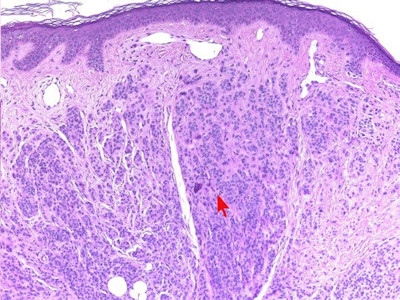

Histologische

variantenDe naevi naevocellularis worden ingedeeld in 3 histologische

varianten

-

junctional naevus (naevus naevocellularis

marginalis): opeenhoping van naevuscellen in de epidermis

dermal

/

intradermal naevus (naevus naevocellularis dermalis):

opeenhoping van naevuscellen in de dermis

compound naevus

(naevus naevocellularis epidermo-dermalis): opeenhoping van naevuscellen in

zowel dermis als epidermis

Zie ook de ingescande PA-coupes (

compound

naevus) van de

afdeling

pathologie van de University of Toronto.